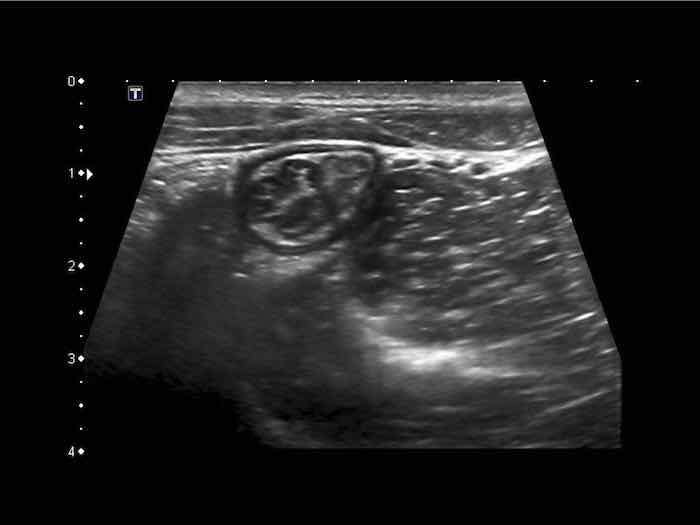

Đây là hình ảnh siêu âm của một trẻ 2 tuổi bị lồng ruột hồi manh tràng từng đợt, được khám trong khoảng thời gian giữa các cơn.

Hồi tràng với nhiều mảng Peyer sa vào manh tràng.

Hình ảnh siêu âm kinh điển của lồng ruột hồi-manh tràng ở hai trẻ khác nhau.

Trong cả hai trường hợp, đoạn hồi tràng bị lồng được định vị không đối xứng bên trong ống lồng ngoài, do mạc treo ruột tăng âm có chứa mỡ, bám vào hồi tràng và đi theo hồi tràng khi bị kéo vào trong.

Trong mạc treo, siêu âm cho thấy một hạch bạch huyết mạc treo (hbh) phóng đại ở cả hai.

Các hạch này phì đại như một phần của tình trạng tăng sản hạch bạch huyết toàn thân và khônghu trú trong lòng hồi tràng.

Do đó đây không phải là điểm dẫn đầu nguyên phát. Ở bệnh nhân bên phải, ruột thừa (mũi tên) cũng bị kéo vào trong.

Lưu ý cấu trúc đa lớp của thành bụng phía trước của phức hợp lồng ruột, đại diện cho ba lớp thành ruột bị gấp lại.